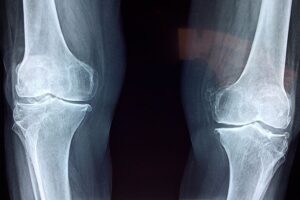

Por qué la rotura de ligamentos es una lesión habitual en el deporte y cuáles son los riesgos

El cirujano traumatólogo Alejandro Druetto advirtió sobre la creciente tendencia a sobrediagnosticar cirugías para lesiones de rodilla, tanto en deportistas